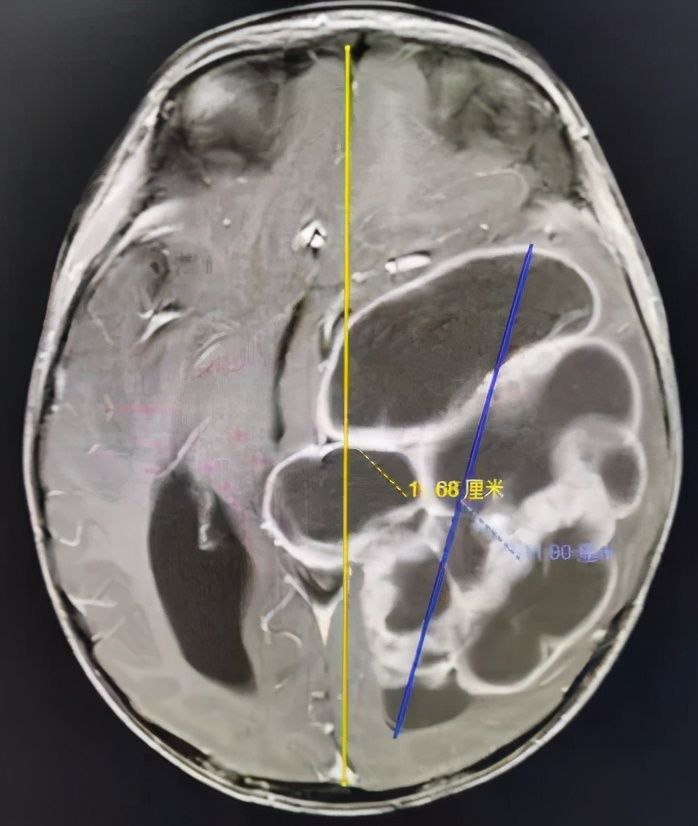

五一假期刚结束,付先生夫妻怀抱2岁儿子小烨,怀着最后一丝希望匆忙赶到中肿找到王翦主任医师。通过仔细检查,王翦主任医师初步判定小烨颅内巨大肿物位于左侧颞顶枕叶,性质考虑恶性室管膜瘤可能性大。肿物巨大,直径达11cm,除了破坏左侧颞顶枕叶脑组织,累及脑室系统并将呼吸和心跳中枢脑干往右侧推移2cm,颅高压明显,随时都可能有生命危险。

脑和心脏一样都是单器官,不同部位的脑有不同的功能,精准调控着人类大部分的身心活动。2岁的小烨头颅最长径15cm,而脑内的肿瘤侵犯了左侧颞顶枕叶等,直径达恐怖的11cm,几乎波及整个左侧大脑!手术是最关键的救命手段,但脑内肿瘤异常巨大,备受病痛折磨的小烨体重仅有11公斤,机体代偿功能非常不完善,手术面临出血性休克、失语和肢体肌力下降等巨大风险。但看着付先生夫妻渴望而无助的眼神,王翦主任医师又一次下决心收治了这一辗转两广多家医院的疑难病例。

术前MR:头的最大直径15cm,而肿瘤直径达到了惊人的11cm